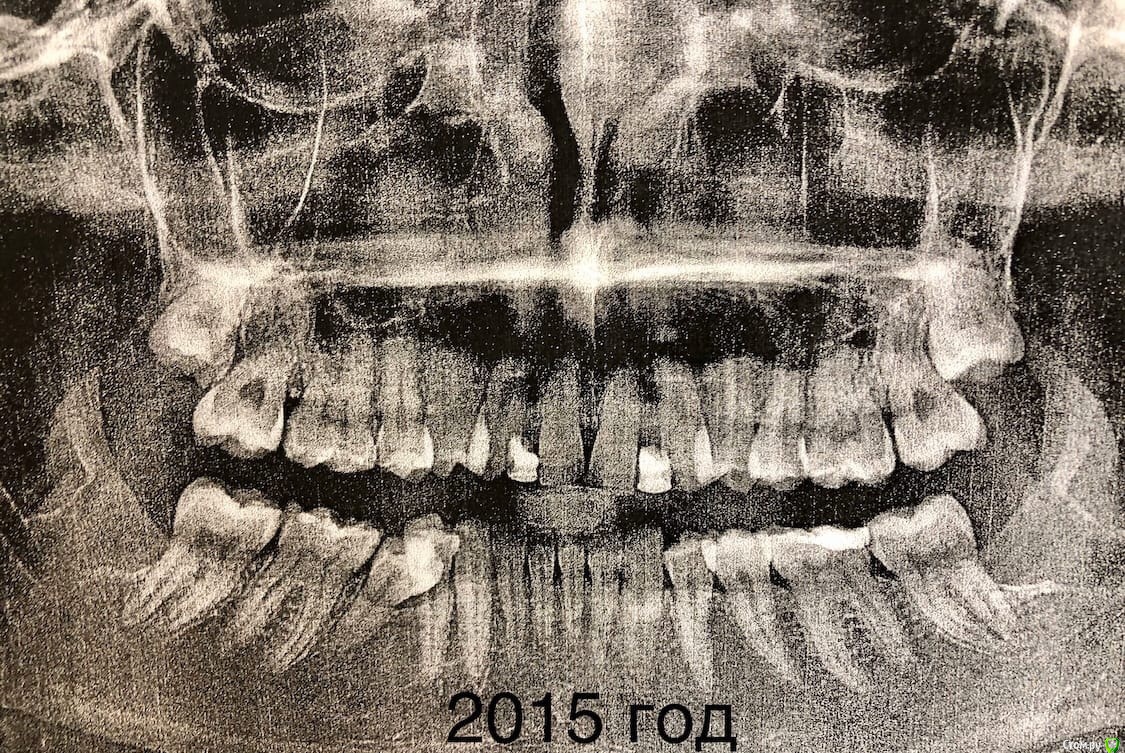

Когда в юности зубы начали меняться, то оказалось что на верхней челюсти отсутствуют резцы, нет зачатков (хотя молочные были).

Врач сказал что это адентия и предложила поставить брекеты.

В 15 Относила брекеты,  раздвинули место под резцы и сделали зубы на стекловолокне мостики, ждали пока буду повзрослей чтобы поставить импланты.

В 20 лет пришла к хирургу что б поставить импланты, он сказал что корни клыков стоят домиком и места под имплант нет, отправил опять к ортодонту.

За 5 лет корни уехали.

Теперь уже другой врач ставит мне опять брекеты и собирает все зубы вместе.

Главная проблема на сегодняшний день в том, что щелкает сустав  (с левой стороны), а челюсть начала уезжать в право.

Врач говорит что все пройдет когда зубы все соберутся, но я не понимаю как, ведь верх меньше на два зуба и нет вообще смыкания контакты нарушены,

да и зубы начали стирать.